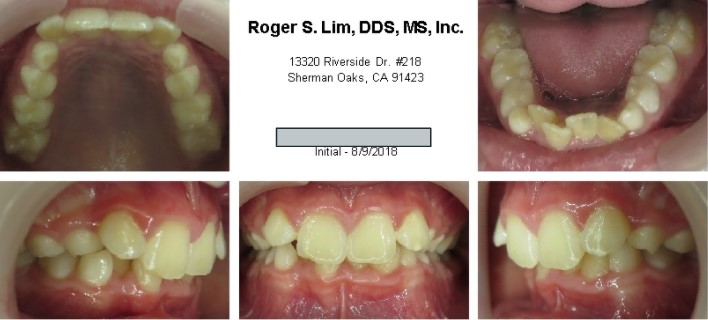

Posterior crossbite before Expander

Posterior crossbite after Expander